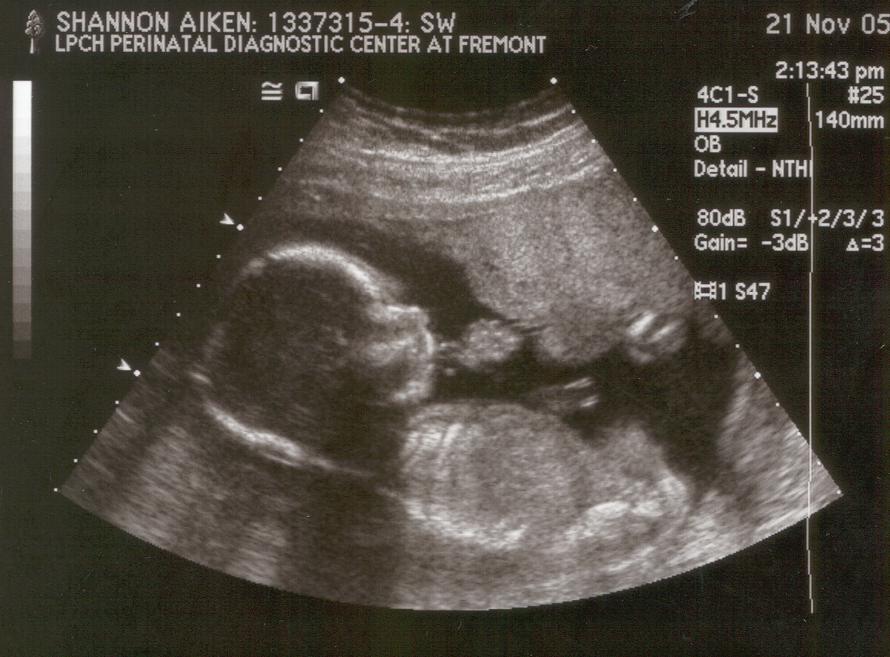

20 weeks: